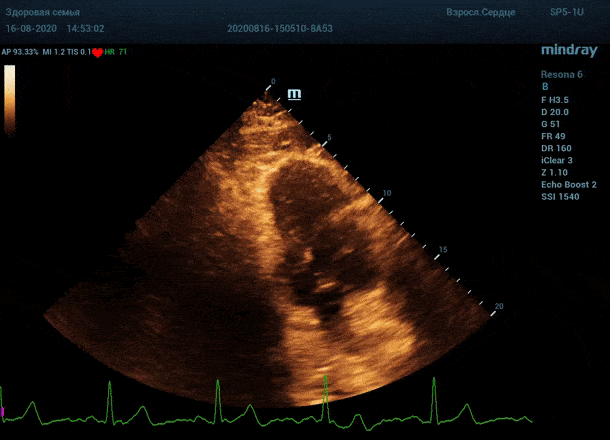

Глаз каждого человека по своей природе уникален. Одни люди лучше видят белый и серый цвет, прекрасно различают все его оттенки. Другим людям проще ориентироваться в голубом, синем и фиолетовом диапазоне, холодных тонах изображения. Однако большинство прекрасно видит оранжевый цвет, и очень четко отличает его от черного – анэхогенного пространства.

Адаптивный колорайзинг - настоящая находка для опытного врача ультразвуковой и функциональной диагностики. Для тренированного глаза открывается новый мир четких контуров, совершенно другой взгляд на привычные структуры сердца.

Данная функция присутствует в большинстве моделей Mindray, с возможностью эхокардиографического исследования. Ограниченное ЭХО окно можно победить разными путями.